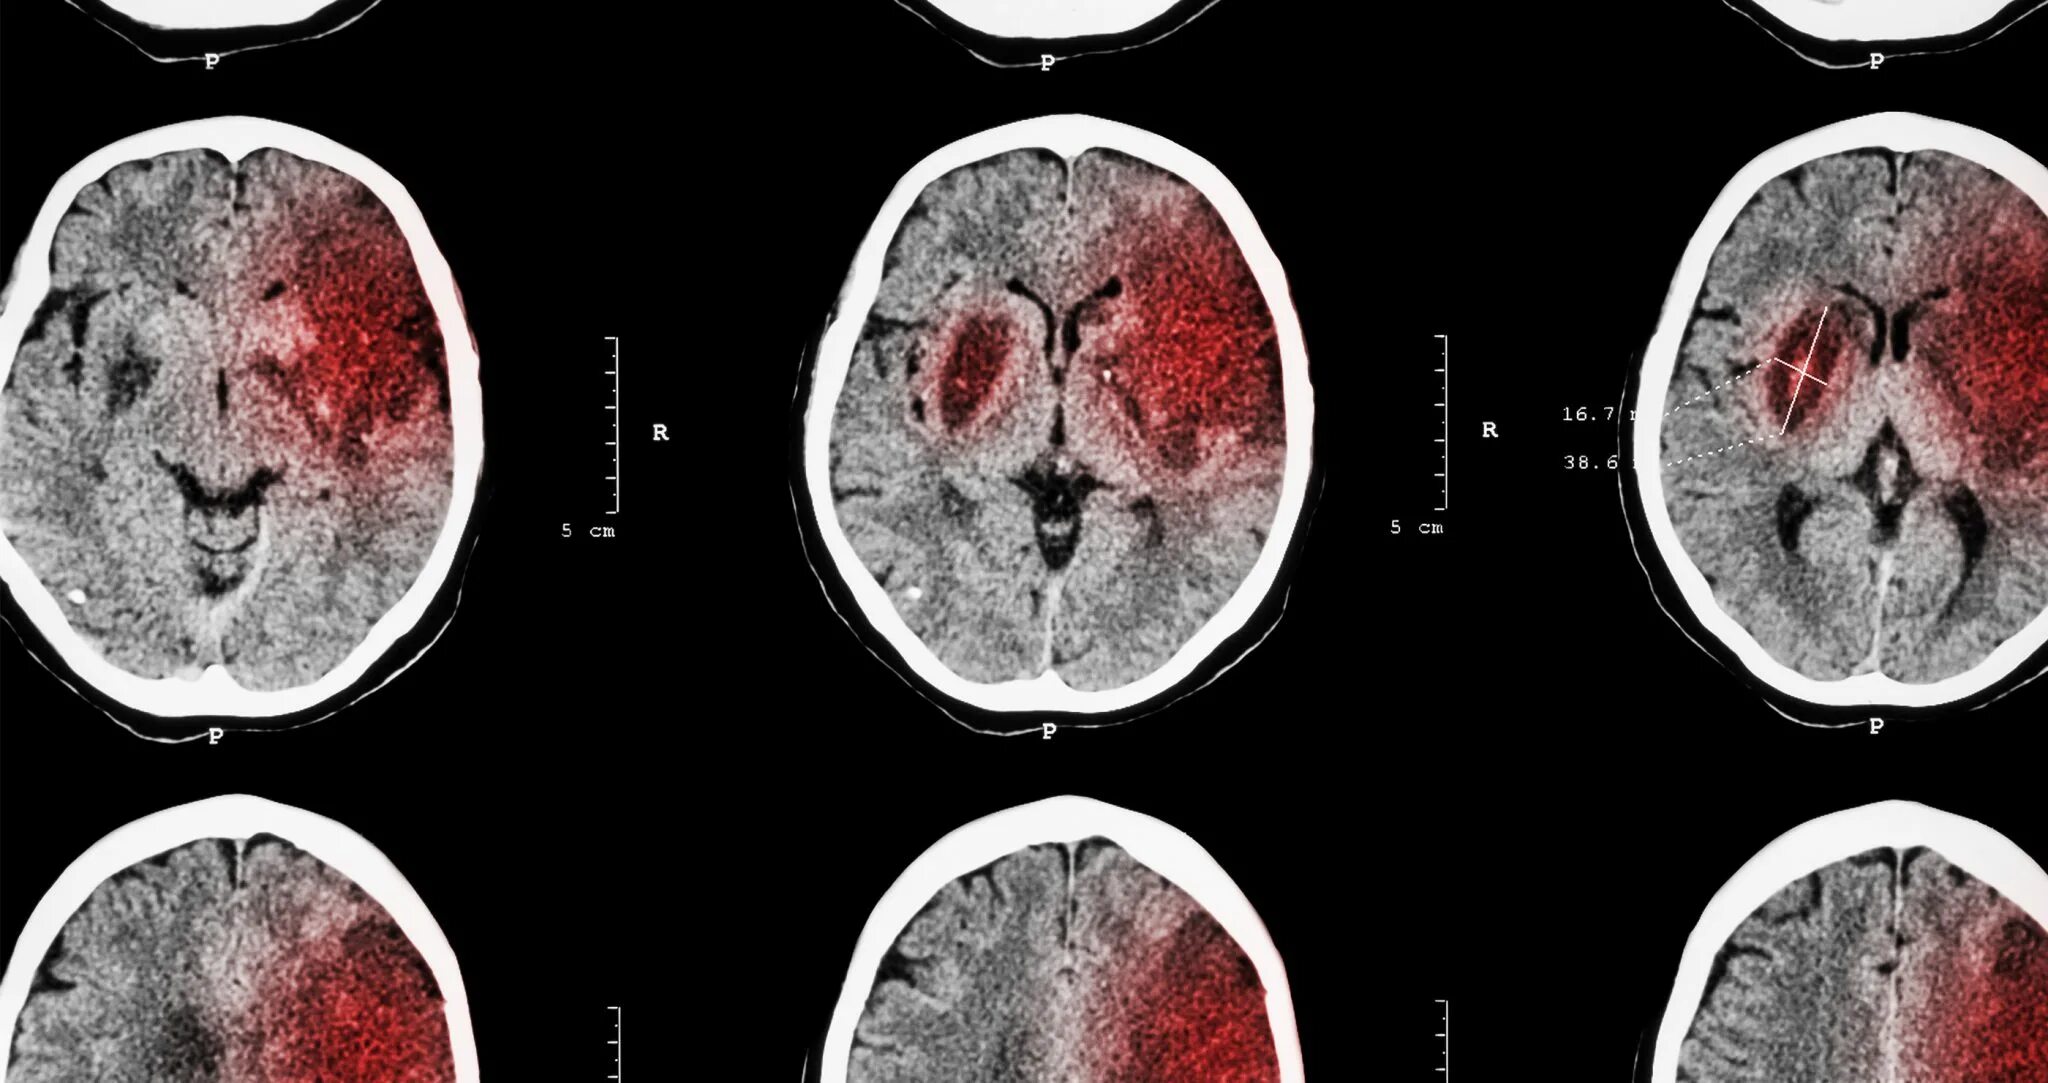

Последствия после инсульта мозга